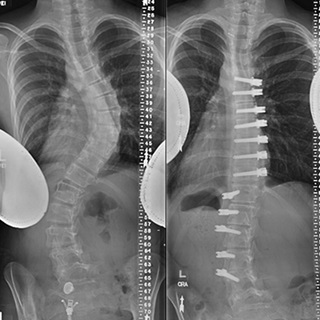

In addition to checking for these differences, the doctor may order X-rays to see the alignment of the vertebrae. These images can be used to determine the degree of spinal curvature and to help monitor its progression over time.

Scoliosis treatment options depend on the degree of curvature of the spine, viewed from the front or back by X-ray. The following are general guidelines for treatment.

Beyond 50 degrees, the spine loses its ability to compensate, and progression becomes inevitable even after physical maturity. The only way to stop progression at this stage is through surgery, either spinal fusion or vertebral body tethering. In spinal fusion surgery, metal implants are used to realign and fuse the vertebrae in a way that corrects the curve.